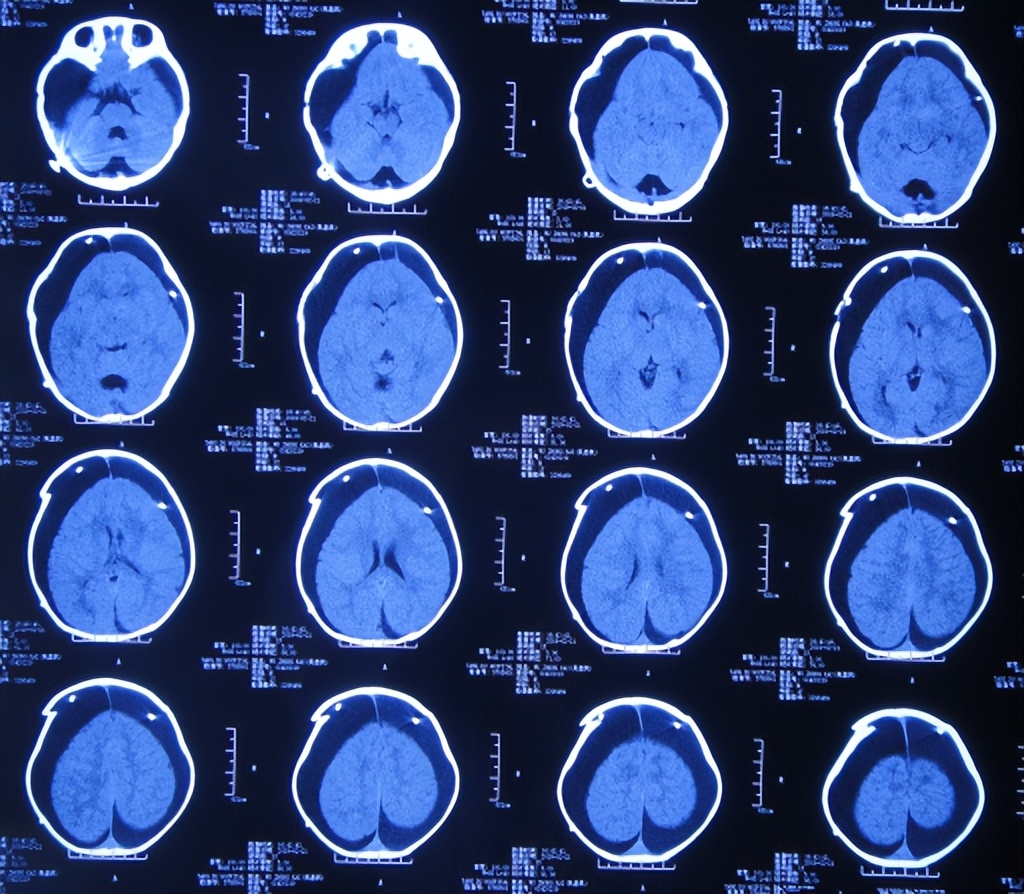

2019年8月12日(李小勇脑脊液治疗4月余)出院,出院时:由入院时的浅昏迷,四肢刺痛后能动,不能哭,半个身体不能动变得精神好有活力,四肢活动正常,家属拉着他的一只手能快速走路,情绪愉悦( 图-36、图-37 );出院时头颅CT示无异常( 图-38 )。

图-38: 出院时头颅CT